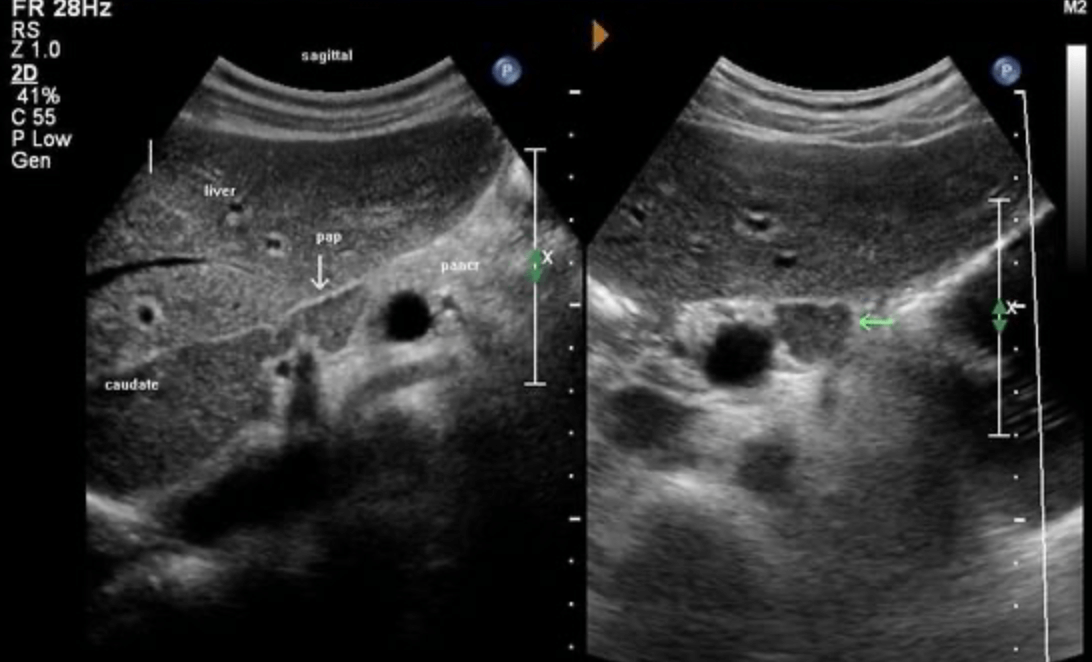

3. Caudate process

Caudate process 미상엽이 아랫부분 우엽까지 확장된 것이다.